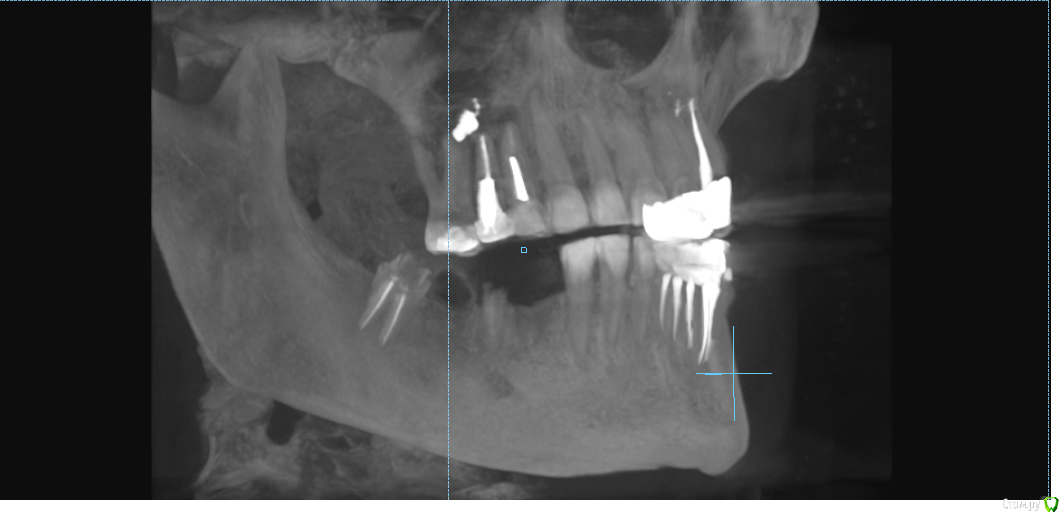

msa Опубликовано 27 февраля, 2019 Поделиться Опубликовано 27 февраля, 2019 Здравствуйте, уважаемые доктора!Прошу совета в выборе оптимального плана лечения и восстановления зубного ряда.Слева вверху (2.3-2.6) мост м/к с 1998 г(со слезами обточила здоровый красивый клык).Справа внизу был мост м/к 2006г на 4.4-4.7 (опорный моляр 4.7 + штифт в 4.5, конструкция была не очень, т.к. не отдала обтачивать под коронку клык 4.3) Через 7 лет мост слетел… От слова совсем.В н/вр пытаюсь понять, нужно ли бороться за премоляр 3.5 Или однозначно удалять? Можно ли сохранить 3.6 с помощью культевой вкладки?Какие варианты оптимального замещения низа справа 4.4-4.7? Корни пока не удаляю. Жизнеспособен ли верх 1.4-1.6? (пломбам больше 20 лет) Скриншоты из КТ от 25.02.19 ОПТГ не делалаСпасибо!С уважением, Марина Ссылка на комментарий

msa Опубликовано 27 февраля, 2019 Автор Поделиться Опубликовано 27 февраля, 2019 (изменено) Нужна ОПТГ или панорамный срез из КТ Получилось немного кривоватокрупно Изменено 27 февраля, 2019 пользователем msa Ссылка на комментарий

kramer Опубликовано 1 марта, 2019 Поделиться Опубликовано 1 марта, 2019 По таким срезам сложно сказать, к тому же без осмотра. Раз врач сказал... Ссылка на комментарий